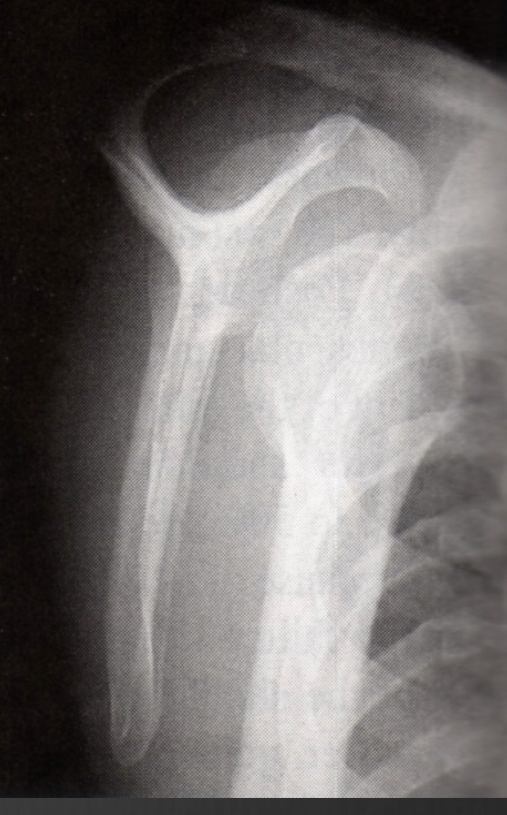

normal trans-scapular y view

normal Y

posterior dislocation lateral to the Y

anterior medial to the Y

axial view of posterior humeral head is oppostie to the corocoid process

normal axial

anterior dislocation axial